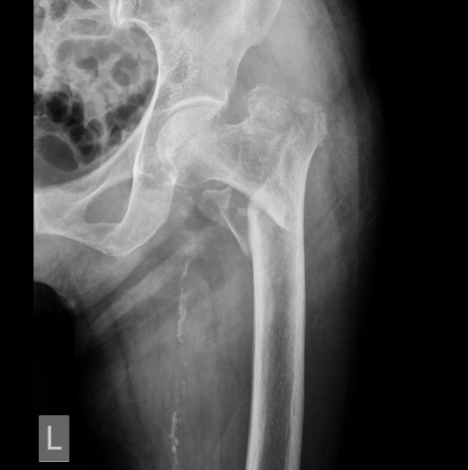

The X-Ray of the left hip:

The above X-ray portrays a left intertrochanteric femur fracture. OUCH!!!